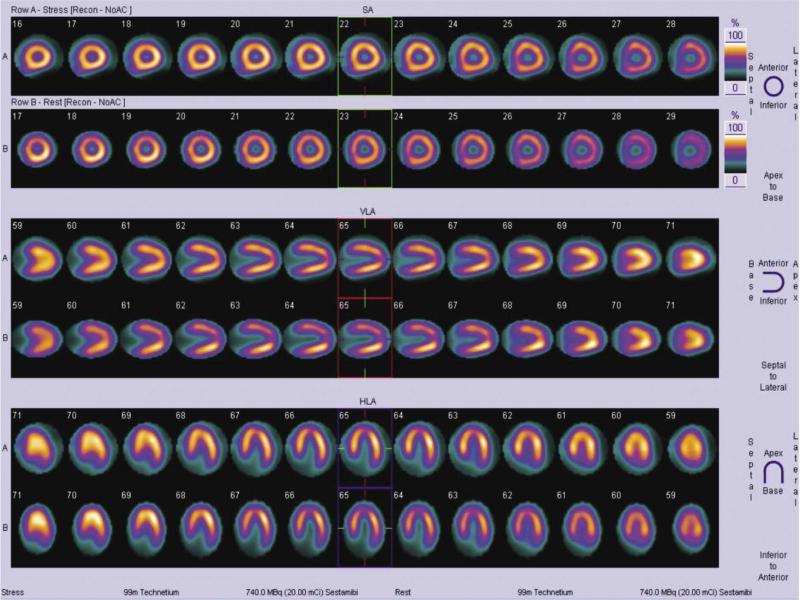

Fig. 2.